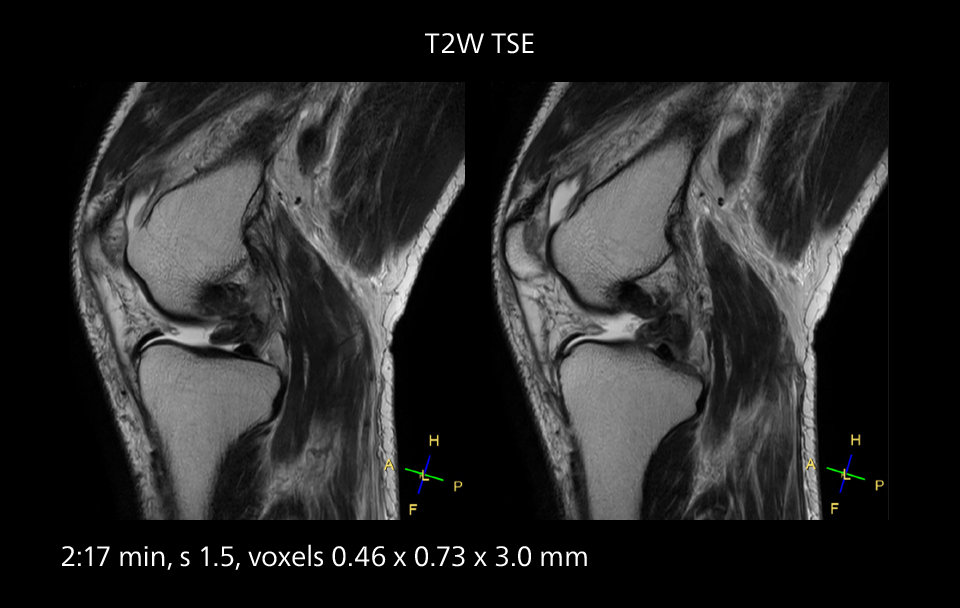

Images showing a posterior cruciate ligament (PCL) tear, a detached medial collateral ligament (MCL) on the tibial side and an intact anterior cruciate ligament (ACL). SmartPath to Elition X helped reduce scan time compared to previous imaging while maintaining resolution.

Sannodai Hospital radiologists had been very satisfied with their Ingenia 3.0T with Compressed SENSE, however after acquiring SmartPath to Elition X they have demonstrated improved image quality and even higher speeds in imaging studies throughout the body, according to Dr. Makuuchi. “Generally, we were impressed by seeing that images are very sharp and have higher SNR than we used to get with our Ingenia 3.0T system,” he notes. “We were delighted to see that high image quality can be obtained in a short time thanks to the Elition with its powerful An example of increased imaging speed is in knee studies. “There is a definite scan time reduction for T2* mFFE and proton density TSE – both of these sequences benefit from much shorter repetition times,” he reports.

Overall, imaging time per sequence has been reduced since the Elition X upgrade. This can help reduce the risk of patient movement and the need for rescans. “As our hospital has many elderly patients, we consider it important to obtain high-quality data in a short time,” Dr. Makuuchi says. “Shorter imaging times are also useful for accepting emergency patients, because faster emergency studies have a reduced impact on the daily examinations schedule. In emergency cases it is also important that high quality images are obtained in a short time.”